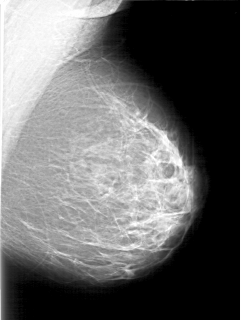

D_4197_1.LEFT_CC

LEFT_MLO LINES 5116 PIXELS_PER_LINE 3841 BITS_PER_PIXEL 12 RESOLUTION 43.5 NON_OVERLAY